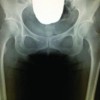

Her right shoulder was also imaged in 2019 and calcific tendinitis was present. Her symptoms were resolved with a course of physical therapy. She did not undergo any serological testing, renal panel, or further hormone workup. On physical examination of the right knee, she had full, pain-free range of motion bilaterally without effusion, lower extremity edema, erythema nor ecchymosis. She did not have any patellar apprehension, crepitus, or tenderness about the patella. She had a stable ligamentous examination including varus and valgus stress at 0 and 30° of flexion. No motor or sensory deficits noted. Her right MCL was tender to palpation along its length, most pronounced near the proximal attachment. We obtained standing PA, standing flexion (Rosenberg), lateral, and sunrise X-ray views demonstrating well-maintained joint space and no soft-tissue swelling. A lobular calcification within the proximal, medial periarticular region of the MCL origin was noted (Fig. 1-4).

At 4 months post-procedure, she continued to report no pain and was able to return to all activities without issue, sleep was no longer pain limited. In addition to resolution of symptoms in her knee, the patient reported no recurrence of pain or dysfunction in her wrist, contralateral knee, or shoulder at over 3 years follow-up. Her physical examination was symmetric and unremarkable. She had full pain free range of motion without effusion or lower extremity edema. She remained stable to varus and valgus stress at 0 and 30° of flexion without discomfort. She had no tenderness about the medial or lateral aspects of her knee. Standing PA, Rosenberg, and sunrise X-ray views of both knees demonstrated interval resolution of calcium deposits within the MCL (Fig. 5 and 6).